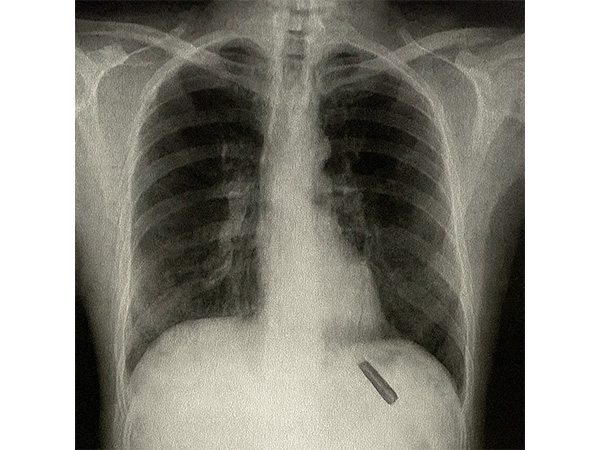

A series of investigations, including an X-ray, revealed the presence of a foreign body in his lung. Considering the risks, the thoracic surgery team led by Dr Sabyasachi Bal, Chairperson at Sir Ganga Ram Hospital, decided to perform the surgery. During the operation, doctors were astonished to discover and successfully extract a 26-year-old plastic pen cap.